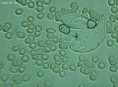

Mnohé štúdie dokazujú pozitívny efekt Bioquantu - jeho laserového žiarenia na postupnú elimináciu baktérií, vírusov či lariev parazitov migrujúcich v krvnom riečišti. Ide najmä o normalizáciu imunity, špecifickej i nešpecifickej. Navyše termodynamický efekt laseru pri ožarovaní krvi, ktorý síce náš organizmus nevníma a ľudské bunky neohrozuje, spôsobuje zvyšovanie termodynamickej teploty najmenších štruktúr - teda mikroorganizmov. Tieto následne ničí aktivovaná imunita a zvýšená baktericídna aktivita krvného séra. Sú zaznamenané pozitívne efekty pri vírusoch HIV/AIDS, vírusoch encefalitídy, pri borelióze, pri prevencii chrípky. O účinkoch na baktérie svedčí aj vysoká účinnosť pri výskytu akné baktérií. Prostredníctvom aktivácie porfírinov sa uvoľňujú voľné radikály a tým zabíjajú baktérie zvnútra..

Laserové ožarovanie krvi navodzuje i úpravu pomerov populácie T helperov a T supresorov smerom k normalizácii a úprave celkového počtu T lymfocytov a vyvoláva zmenu aktivity enzýmov imunokompetentných buniek. To je dôležité pre celom rade ďalších ochorení.